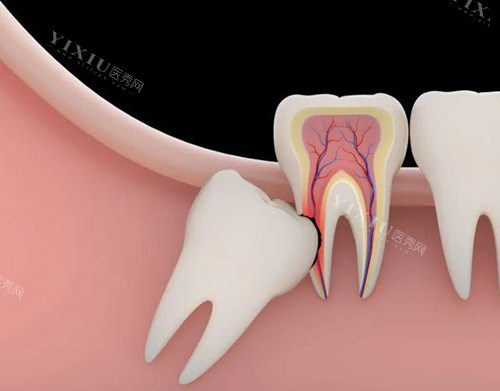

智齿拔除(简单):300元起

智齿拔除(复杂):1000元起